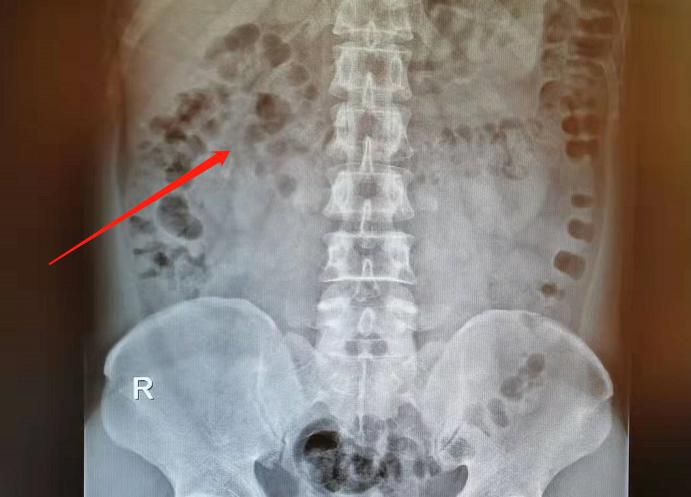

△體外碎石前。

△體外碎石後。